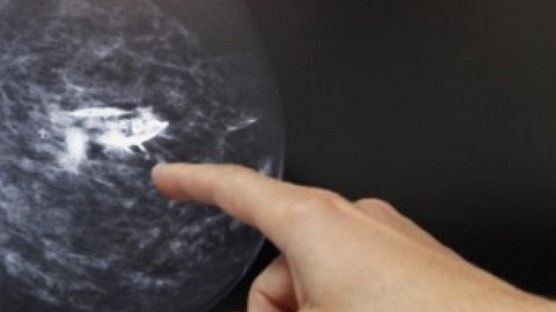

11 apr. 2016, 10:58ActualAvea un semn ciudat pe sânul stâng. S-a dus la doctor şi iată ce a descoperit!